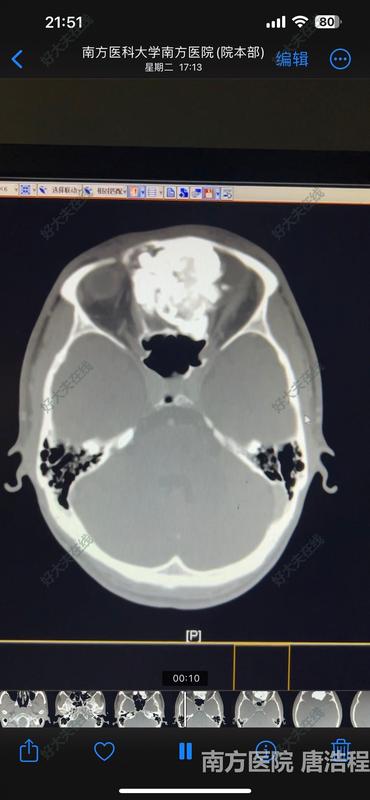

腦干腫瘤,竟然是罕見的神經(jīng)鞘瘤!

9歲的男孩小明(化名),經(jīng)常早上起來嘔吐,伴有咳嗽、咳痰,看了許久也不見好轉(zhuǎn)。醫(yī)生建議查個頭顱CT,不查不要緊,一查嚇一跳,發(fā)現(xiàn)腦干上長了個東西。于是連忙安排檢查頭顱磁共振發(fā)現(xiàn)腦干的延髓段真的有一個巨大的腫瘤。眾所周知,腦干是人腦的中樞,而延髓是又腦干最核心的部分,體積不大,但關(guān)系到運動、心跳、呼吸等多種生命最重要的作用。是真正意義上的生命中樞。腫瘤不偏不倚正好在延髓,使其明顯受壓。但患者目前除了有咳痰增加外,幾乎沒什么癥狀,而且四肢手腳活動完全正常,吞咽、咳痰等功能也正常。因此手術(shù)切除腫瘤具有極大的風(fēng)險,稍有不慎,便會引起癱瘓,甚至影響吞咽、咳嗽以及呼吸功能,后果不堪設(shè)想。多方打聽,咨詢了全國很多大醫(yī)院的專家,有的說是室管膜瘤,還有的說是實質(zhì)性血管母細(xì)胞瘤等等。但都說手術(shù)風(fēng)險極大,有可能無法全切腫瘤并導(dǎo)致癱瘓或者咳痰、呼吸功能障礙。手術(shù),目前患者沒什么明顯的癥狀和異常,一旦出問題,后果不堪設(shè)想,家屬難以接受;不手術(shù),腫瘤很大了,可能遲早會引起癱瘓等嚴(yán)重的后果。家屬因此陷入極大的糾結(jié)之中。經(jīng)人介紹找到我們,仔細(xì)了解病情和影像后,詳細(xì)和家屬闡明了病變可能的性質(zhì)和手術(shù)的價值。征得家屬的理解,決定為小明進(jìn)行腦干腫瘤手術(shù)。通過仔細(xì)研究術(shù)前CT和磁共振,我們認(rèn)為室管膜瘤和血管母細(xì)胞瘤的可能性小,更像罕見的腦內(nèi)神經(jīng)鞘瘤。術(shù)前為患者進(jìn)行了詳盡的神經(jīng)功能評估,發(fā)現(xiàn)患者除了左下肢感覺誘發(fā)電位輕度異常外,四肢運動、感覺功能均正常,吞咽、咳嗽功能和喉鏡檢查均未發(fā)現(xiàn)異常。這也為手術(shù)帶了極大的挑戰(zhàn)。我們采取枕后正中入路,為患者進(jìn)行手術(shù),術(shù)中發(fā)現(xiàn)腫瘤位于腦干內(nèi),并向外生長。術(shù)中冰凍病理提示可見梭形細(xì)胞,神經(jīng)鞘瘤首先考慮。與典型的神經(jīng)鞘瘤不同的是,雖然腫瘤對起源于脊髓上的頸神經(jīng)根和后組顱神經(jīng)有包繞,但還是能夠通過顯微手術(shù)完全分離,并沒有發(fā)現(xiàn)腫瘤起源于上述神經(jīng)。同時,腫瘤與周邊顱底的硬腦膜完全沒有附著,因此也排除了腦膜瘤的可能性。通過精細(xì)手術(shù),我們徹底將腫瘤完全從腦干上分離下來,并保證了腦干的完整性。手術(shù)成功全切腫瘤。術(shù)后患者神經(jīng)功能完全保留,四肢活動良好。從住院到康復(fù)出院,僅僅8天時間。顱內(nèi)神經(jīng)鞘瘤大約占顱內(nèi)腫瘤的8%,大多數(shù)起源于第八對前庭神經(jīng),也就是常說的聽神經(jīng)瘤。真正起源于腦內(nèi)神經(jīng)鞘瘤不到顱內(nèi)神經(jīng)鞘瘤的1%。迄今為止,也僅僅只有70余例的臨床報道(實際可能會更多一些)。而腦干內(nèi)的神經(jīng)鞘瘤就更受之又少了。發(fā)生機(jī)制及其來源目前仍不是很清楚,可能是由血管周圍神經(jīng)叢的許旺氏細(xì)胞發(fā)生的,也可能是軟腦膜向許旺氏細(xì)胞的轉(zhuǎn)化引起的異位神經(jīng)鞘瘤??傊捎诓±∩?,這方面的研究不是很多。該病多兒童和年輕人,男性多見。而小明僅僅只有9歲,更是目前已知年齡最小的患者。對于腦干腫瘤,雖然手術(shù)難度高、風(fēng)險大,但也并非以往所認(rèn)為的手術(shù)禁區(qū)。我們經(jīng)過術(shù)前認(rèn)真評估、全面準(zhǔn)備,術(shù)中精細(xì)操作,加上新華醫(yī)院0到100歲全年齡段ICU團(tuán)隊專業(yè)的圍手術(shù)期處理,變不可能為可能,讓腦干腫瘤患者一樣可以得到非常滿意的結(jié)果。